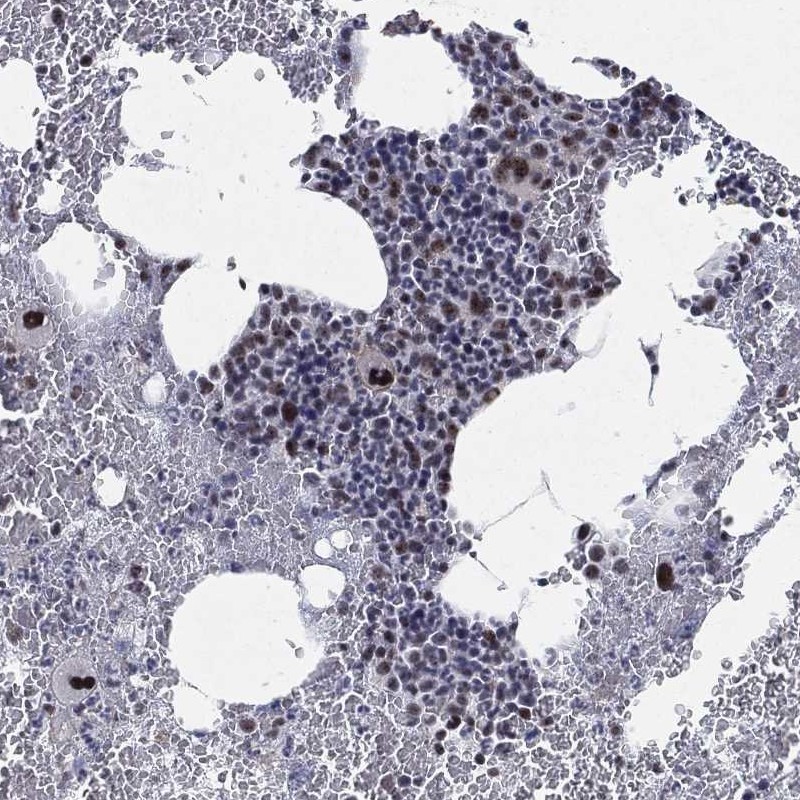

Immunohistochemical staining of human bone marrow shows strong nuclear positivity in hematopoietic cells.